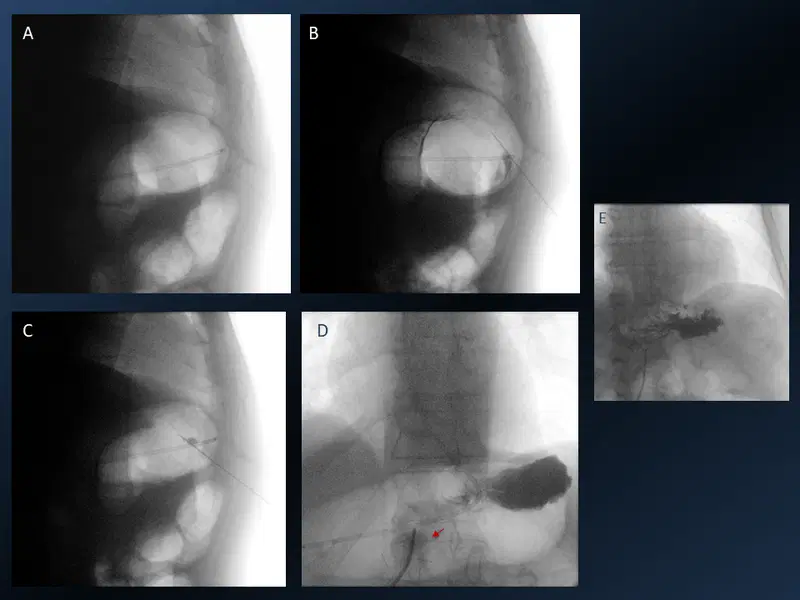

Transarterial Chemoembolization

Fifty-four-year-old lady with non-cirrhotic liver and HCC. Treated with transarterial chemoembolization (TACE). A. CECT of the abdomen – arterial phase enhancing lesion in segment VII of the liver. B. Selective celiac artery cannulation with a 4F Simmons diagnostic catheter which was advanced to the common hepatic artery (blue arrow) and a microcatheter (red arrow) was coaxially placed with the tip in the RHA. Superselective cannulation and angiogram of the feeder artery, a branch of right hepatic artery showing tumor blush (*) along with normal parenchymal branches (black arrow). C. Further advancement of the microcatheter (red arrow) to surpass the normal parenchymal branches and chemoembolization (Lipiodol and Doxorubicin emulsion in 2:1 ratio) in process. Lipiodol accumulation in the tumor stroma (*).  After chemoembolization, gel foam embolization of the feeder artery was done. Post embolization angiogram showed complete occlusion of the tumor artery with patent normal parenchymal branches (arrow). Good lipiodol โ€“doxorubicin emulsion deposit is also seen (*).